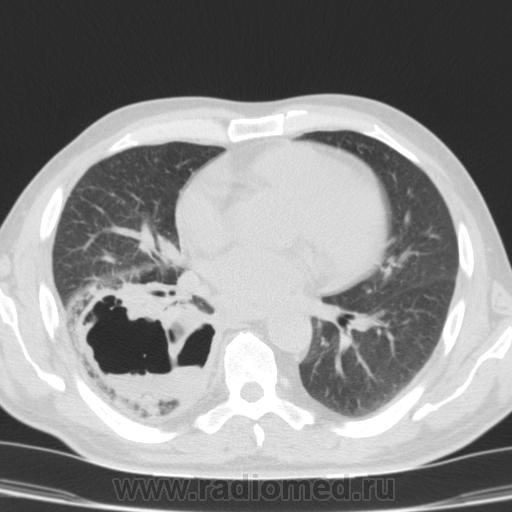

Здравствуйте, коллеги! Не откажите в помощи интерпретировать этот хаос в легких. После переохлаждения больной обратился за медиц помощью только через 1 месяц, в первые 2 недели была температура до 38*, сейчас после лечения самочувствие улучшилось, направлен на КТ контроль после лечения пневмонии. Подскажите, какой выставить диагноз?

Полость в нижней доле правого легкого, неправильной формы, с вовлечением и сдавлением бронхов, с уровнем жидкости. Отмечается утолщение костальной плевры с небольшим количеством жидкости. Не исключается инфекционная деструкция или новообразование правого нижнедолевого бронха, с ателектазом и деструкцией.

Дренированный абсцесс нижней доли справа.

Согласен с тем, что это - абсцесс(я бы даже сказал - абсцедирующая гангрена) нижней доли правого лёгкого.Коллега Nikolas, совершенно справедливо, характеризовал это состояние как промежуточное между абсцессом и гангреной.

Главное отличе абсцесса и гангрены не состояние(нет!И при абсцессе оно может быть тяжелейшим, со сдвигом лейкоцитарной формулы до миелоцитов, гектическими размахами температуры, тяжелейшей интоксикацией, даже с токсической острой почечной недостаточностью), а МОРФОЛОГИЯ. Абсцесс менее распространенный и всегда ограниченный. Гангрена - очень распространенная (вся доля, все легкое даже) и не имеет четких границ. Здесь - большая распространенность(вся доля), но есть четкая граница.